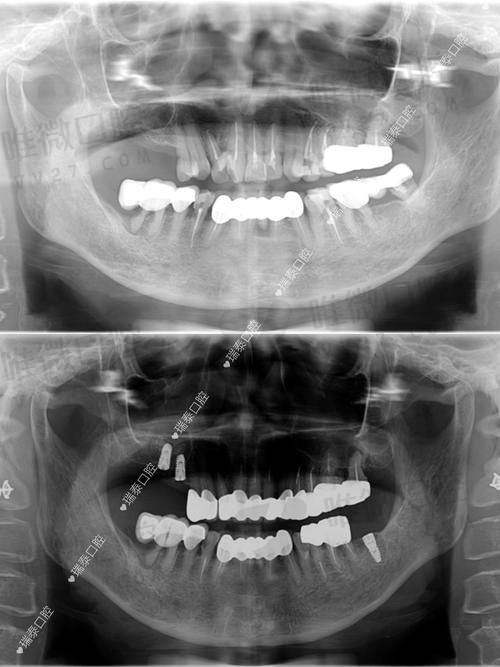

作为连锁医美品牌,宁波美莱不仅在皮肤抗衰领域拔得头筹,口腔中 心在种植牙技术方面也非常专精。他们采用德国和瑞士等高端种植体品牌,如费亚丹、iti和诺贝尔,手术主要以微创种植为主,还配备CBCT精细数据分析系统,上岗医生如李斌与张玉涛在局部种牙方面经验多。价格方面也意外地亲民,例如韩系登腾种植牙仅4500元起,适合预算型人群。

牙博士在宁波有多个院区,几乎覆盖了每个大型住宅密集区,医院配备3D导板微创种植技术,医生团队中像王道军、牟宗起均是高难种牙领域的佼佼者。这里较大优势是技术齐全,从穿颧穿翼、即刻负重到All-on-4半全口修复都能驾轻就熟,同时价格也较为亲民,让一些牙槽骨条件欠佳的客户也能负担得起。

主打数字化导航种植技术,是拥有较强技术背景的私立机构。该院对All-on-4/6全口种牙较为熟练,相关医生多为国有医院出身,如一些三等甲院校退役医生,方案制定严谨。硬核科技加传统经验,是这家医院较大优势。

佳兴通过CBCT和全景数字系统辅助种植,擅长处理高龄不适合手术类型的个案,并支持延迟种植、一次性种植、即刻修复等多种方法选择。医生团队拥有临床实操经验,非常注重术后咬合调节和美观度保持。